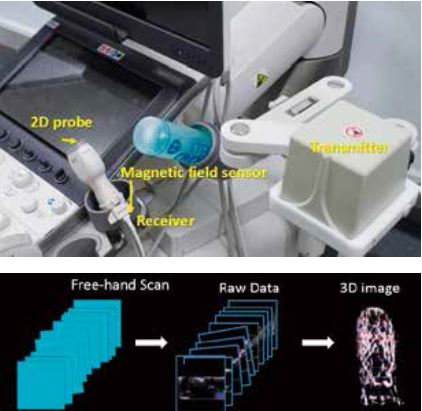

Smart Sensor 3D - це новітня технологія об'ємного сканування. Зображення, отримані шляхом сканування "вільною рукою" за допомогою 2D-датчика, об'єднуються для створення 3D-зображень високої чіткості з точною позиційною інформацією, отриманою за допомогою магнітного поля від датчика (Рис. 1).

Рисунок 1. Основний принцип роботи Smart Sensor 3D